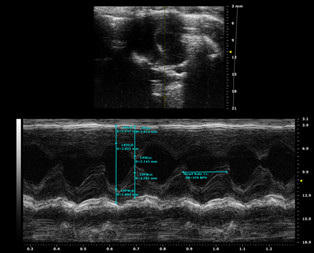

模型評價

3573634484425250063-14

圖注:TAC造模前心電圖

圖注:模型前正常SD大鼠B超圖

66552255